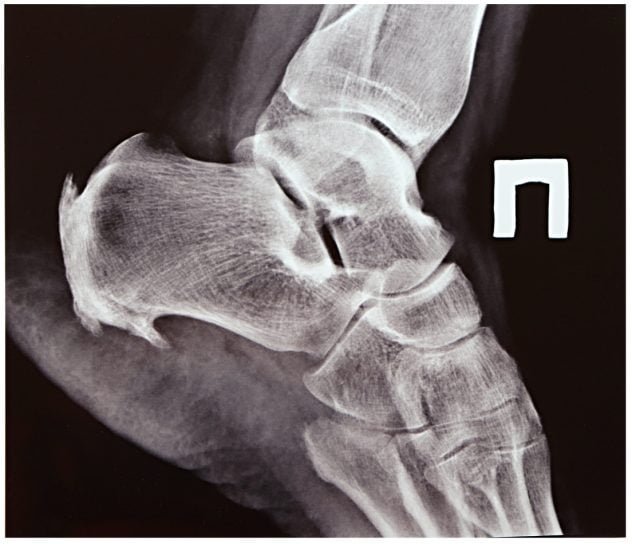

Domů jsme přijeli v neděli a já hned druhý den vyrazil k odbornému lékaři. Na povel jsem se zul, sundal ponožky a vylezl na vyšetřovací lůžko. Pan doktor si vyhrnul rukáv, zvedl mou nohu a v jednom místě zatlačil. Zařval jsem a provedl všechny potřebné i tělesné úkony k tomu, abych si necvrkl do kalhot. Pak mi pan doktor oznámil, co jsem již i tak pochopil: „Není to dobré.“ Pak vypsal žádanku a já jsem vyrazil na rentgen. Je úžasné, co vše se v nás může skrývat. Dvě bezmála třícentimetrové ostruhy se na mne ze snímku smály jako ty nejjedovatější smajlíky. Znovu jsem musel vylézt na lůžko a pan doktor začal ulamovat skleněné vršky ampulek a jejich obsah nasávat do stříkačky naprosto nerozumných rozměrů. Padly na to celkem tři ampule. Kortikoidy, analgetika a ještě cosi, co si již, zaplaťpánbu, nepamatuji. Zatnul jsem zuby, zavřel oči a děkoval prozřetelnosti, že jsem si před tím odskočil na WC. Kde kdo se stará o týraná zvířata. No a co já?!